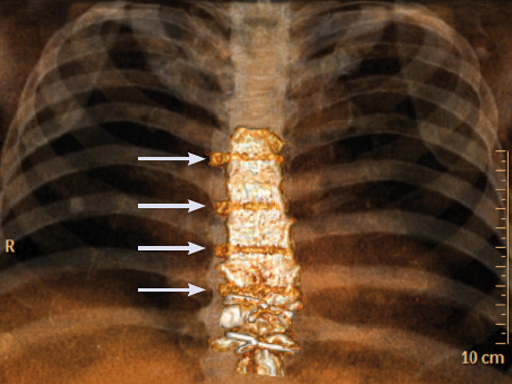

Case 2: A 55-year-old woman, who previously underwent ventricular septal defect closure at 5 and aortic valve reconstruction at 31, required aortic valve replacement due to symptomatic aortic valve insufficiency.

The patient was morbidly obese with a BMI of 45. Due to the high risk for sternal instability and/or deep sternal wound infection, closure was performed using the sternal zipfix system. The zipfix provides quick and reliable stable fixation of the sternum even in patients that are at a higher risk to develop a sternal instability or a deep sternal wound infection.

The postoperative course was uneventful and the patient was discharged on postoperative day 7 with no signs of sternal instability or wound healing problems. At 18 months follow-up the wound had healed completely and the sternum was stable, with no signs of infection.